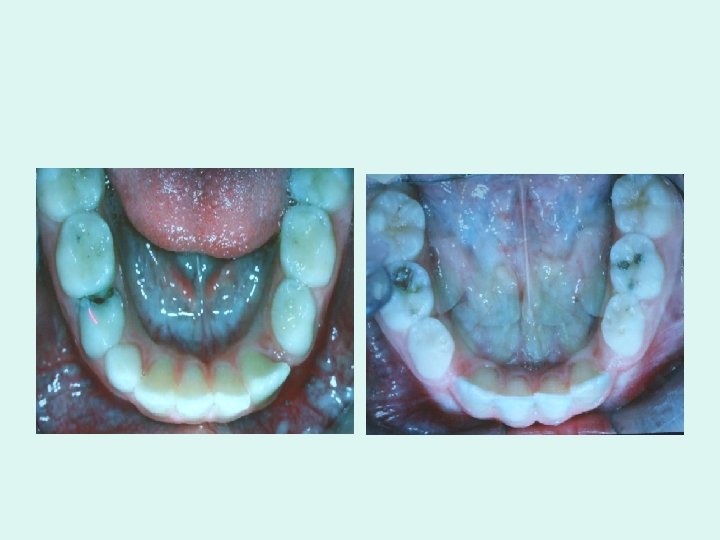

POSTNATAL PREVENTION • Prolonged retention of deciduous teeth can delay the eruption of its permanent successor or deviate the permanent successor from its normal course of eruption. Deflection of the permanent teeth is most commonly seen in the anterior region, where it may cause permanent incisors to erupt labially or lingually of the dental arch. In order to prevent it, the deciduous tooth should be extracted as soon as possible.